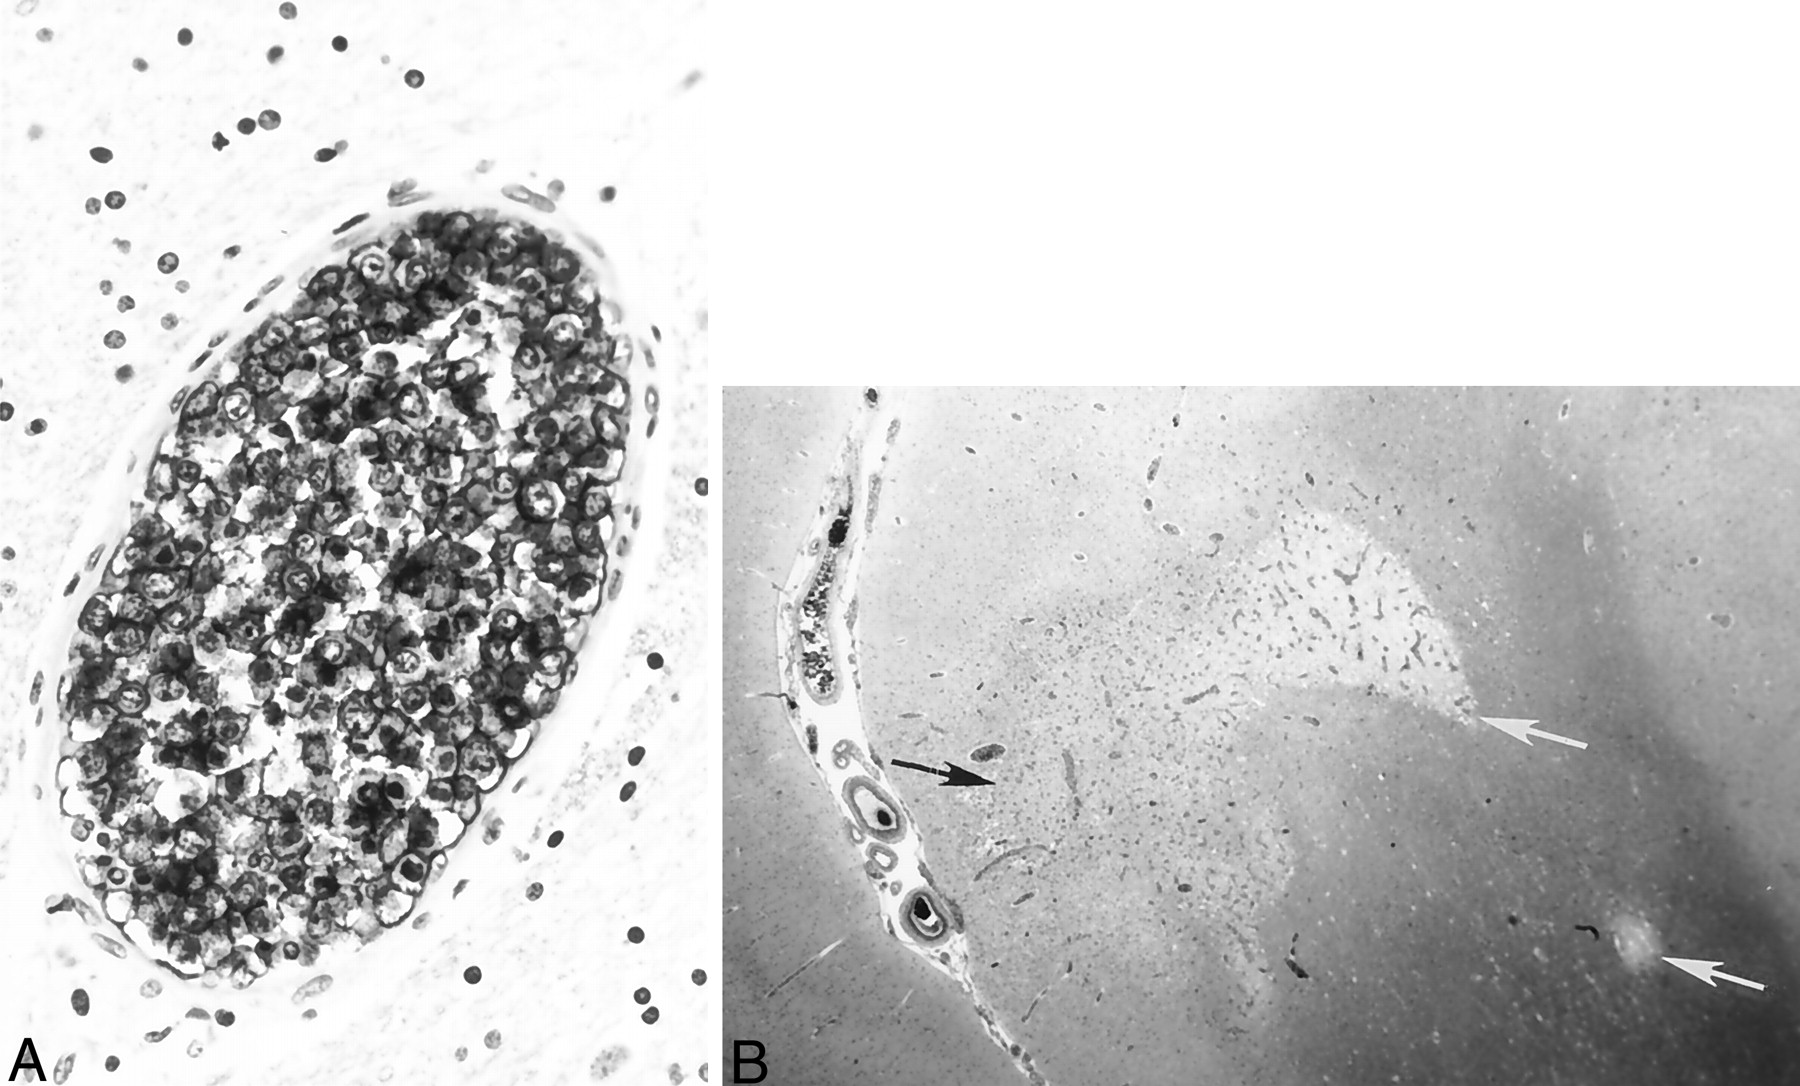

Histologic specimens confirming ALCL.

A, Immunostaining with L26, a monoclonal antibody B cell marker, reveals large, atypical intravascular tumor cells occluding the lumen of a small cerebral blood vessel. Note the large ratio of vessel diameter to wall thickness, indicative of neoplastic lymphocytes occluding and distending the vessel lumen. In contrast to a true vasculitic process, the vessel wall itself does not show inflammatory damage.

B, Hematoxylin and eosin staining shows gray (black arrow) and white (white arrows) matter infarctions resulting from blood flow compromised by intravascular lymphoma.